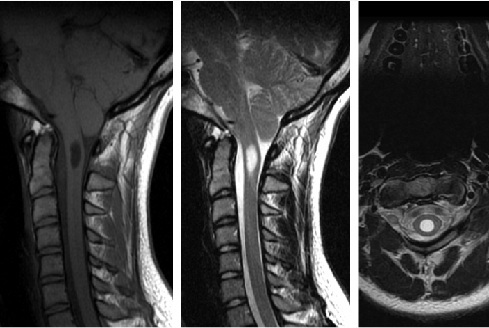

Apakah diagnosis yg plg mgkn terlihat pada MRI?

B. Chiari 1 malformasi

The correct answer is Chiari 1 malformation.

There is cerebellar tonsillar ectopia (approximately 1 cm below the foramen magnum) with an associated cervical syrinx, findings consistent with Chiari 1 malformation. The contents of the syrinx correspond to CSF (i.e. T1 hypointense and T2 hyperintense). The lesion has distinct margins and displaces rather than infilatrates adjacent spinal cord.

Astrocytomas are infiltrating tumors. Basilar invagination refers to narrowing of the foramen magnum due to upward migration of the top of the C2 vertebrae. Multiple sclerosis causes demyelinating lesions of the brain and spinal cord and is not associated with tonsillar ectopia. Chordomas are primary bone tumors of notochord remnants that are extradural in location.